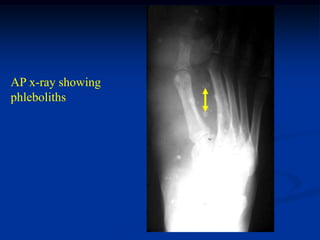

CLASSIC

Case #292

14 year female

hemangioma foot

AP x-ray showing

phleboliths

Lateral x-ray showing more phleboliths

tumor

Axial T-1 MRI

Axial T-2 MRI

Gross specimen with hemorrhagic cysts

Photomic

CLASSIC Case #292 14 year female hemangioma foot

• 270.

• 271.

Lateral x-ray showingmore phleboliths